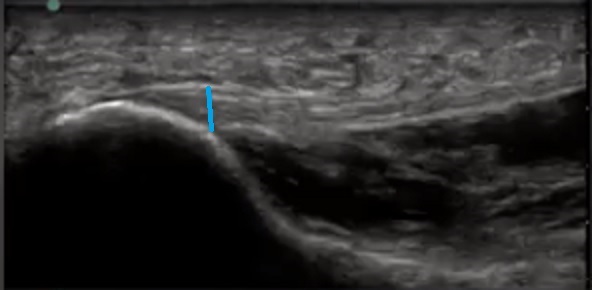

Bild: Fuß und Sprunggelenk, Messung der Aponeurosis plantaris

• Blaue Linie: Dicke der Aponeurosis plantaris